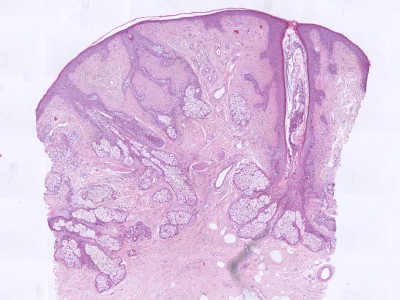

PA:Verticaal georiënteerde

dermale laesie bestaande uit een haarfollikel van waaruit dunne strengen

cellen met sebocyten of talgklier lobuli uitwaaieren naar het omgevende

stroma. Soms cystische dilatatie van het infundibulum. Het omgevende stroma

bevat mucine en parallele vezels fibrillair collageen, fibroblasten en soms

enkele dendritische cellen.

ingescande coupe (zoom) |